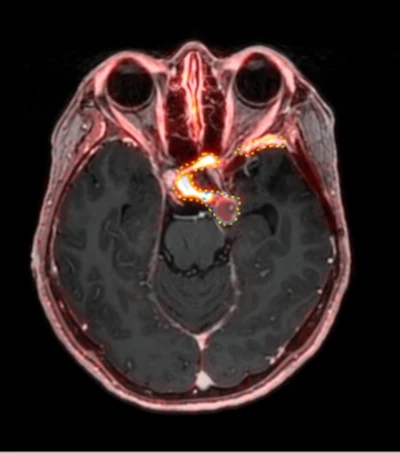

A 53-year-old patient (patient number four) with a recurrent pituitary adenoma with extension of a cystic component of disease to the medial temporal lobe apparent on MRI (contoured in blue), and extension of disease to the left sphenoid bone and orbital apex apparent on [68Ga]Ga-DOTA-TATE (contoured in yellow).Clinical and Translational Radiation Oncology

Average PET volumes were both larger and smaller than average MRI volumes for different patients. The range of differences between average MRI and PET volumes was −3.81 cm3 to +4.34 cm3. Lastly, there was a median absolute difference between average PET and average MRI volume of 2.24 cm3, which corresponds to a median relative percent difference of 20.3%, according to the authors.